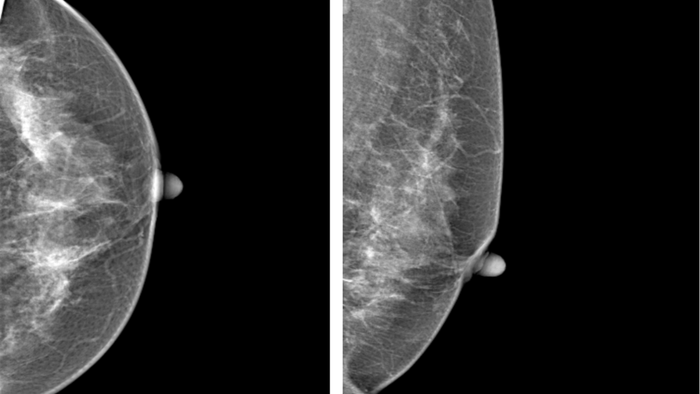

Hình ảnh phim chụp Xquang tuyến vú trái của bệnh nhân H. theo hướng CC và MLO

Theo ThS.BS Nguyễn Văn Quế, phụ trách nhóm chuyên sâu hình ảnh học tuyến vú - Bệnh viện Đại học Y Hà Nội, "đây là một ca đặc biệt. Tổn thương của chị H. thuộc dạng không tạo khối, kích thước rất nhỏ, nằm trong mô vú đặc - nếu chỉ xem bằng mắt thường, bác sĩ dễ bỏ sót".

Khi hình ảnh được phân tích bằng phần mềm trí tuệ nhân tạo, hệ thống đã khoanh vùng khu vực nghi ngờ chỉ vài milimet. Sau khi chụp ép phóng đại, tổn thương trở nên rõ nét hơn. Kết quả sinh thiết xác định: ung thư vú giai đoạn sớm.